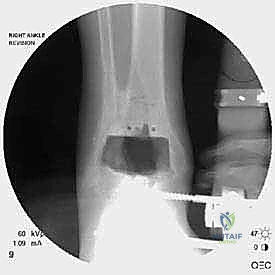

TECH FIG 2 • Lateral malleolus fracture. The lateral approach is chosen ( A ), and the fracture fragments are exposed and curetted ( B ).

TECH FIG 2 • Clinical photograph reveals contouring of plate ( E ) and screw fixation above and below the fracture to maintain stability.

TECH FIG 2 • Intraoperative fluoroscopy demonstrates the fracture location ( C ) and reduction with plate fixation ( D ).